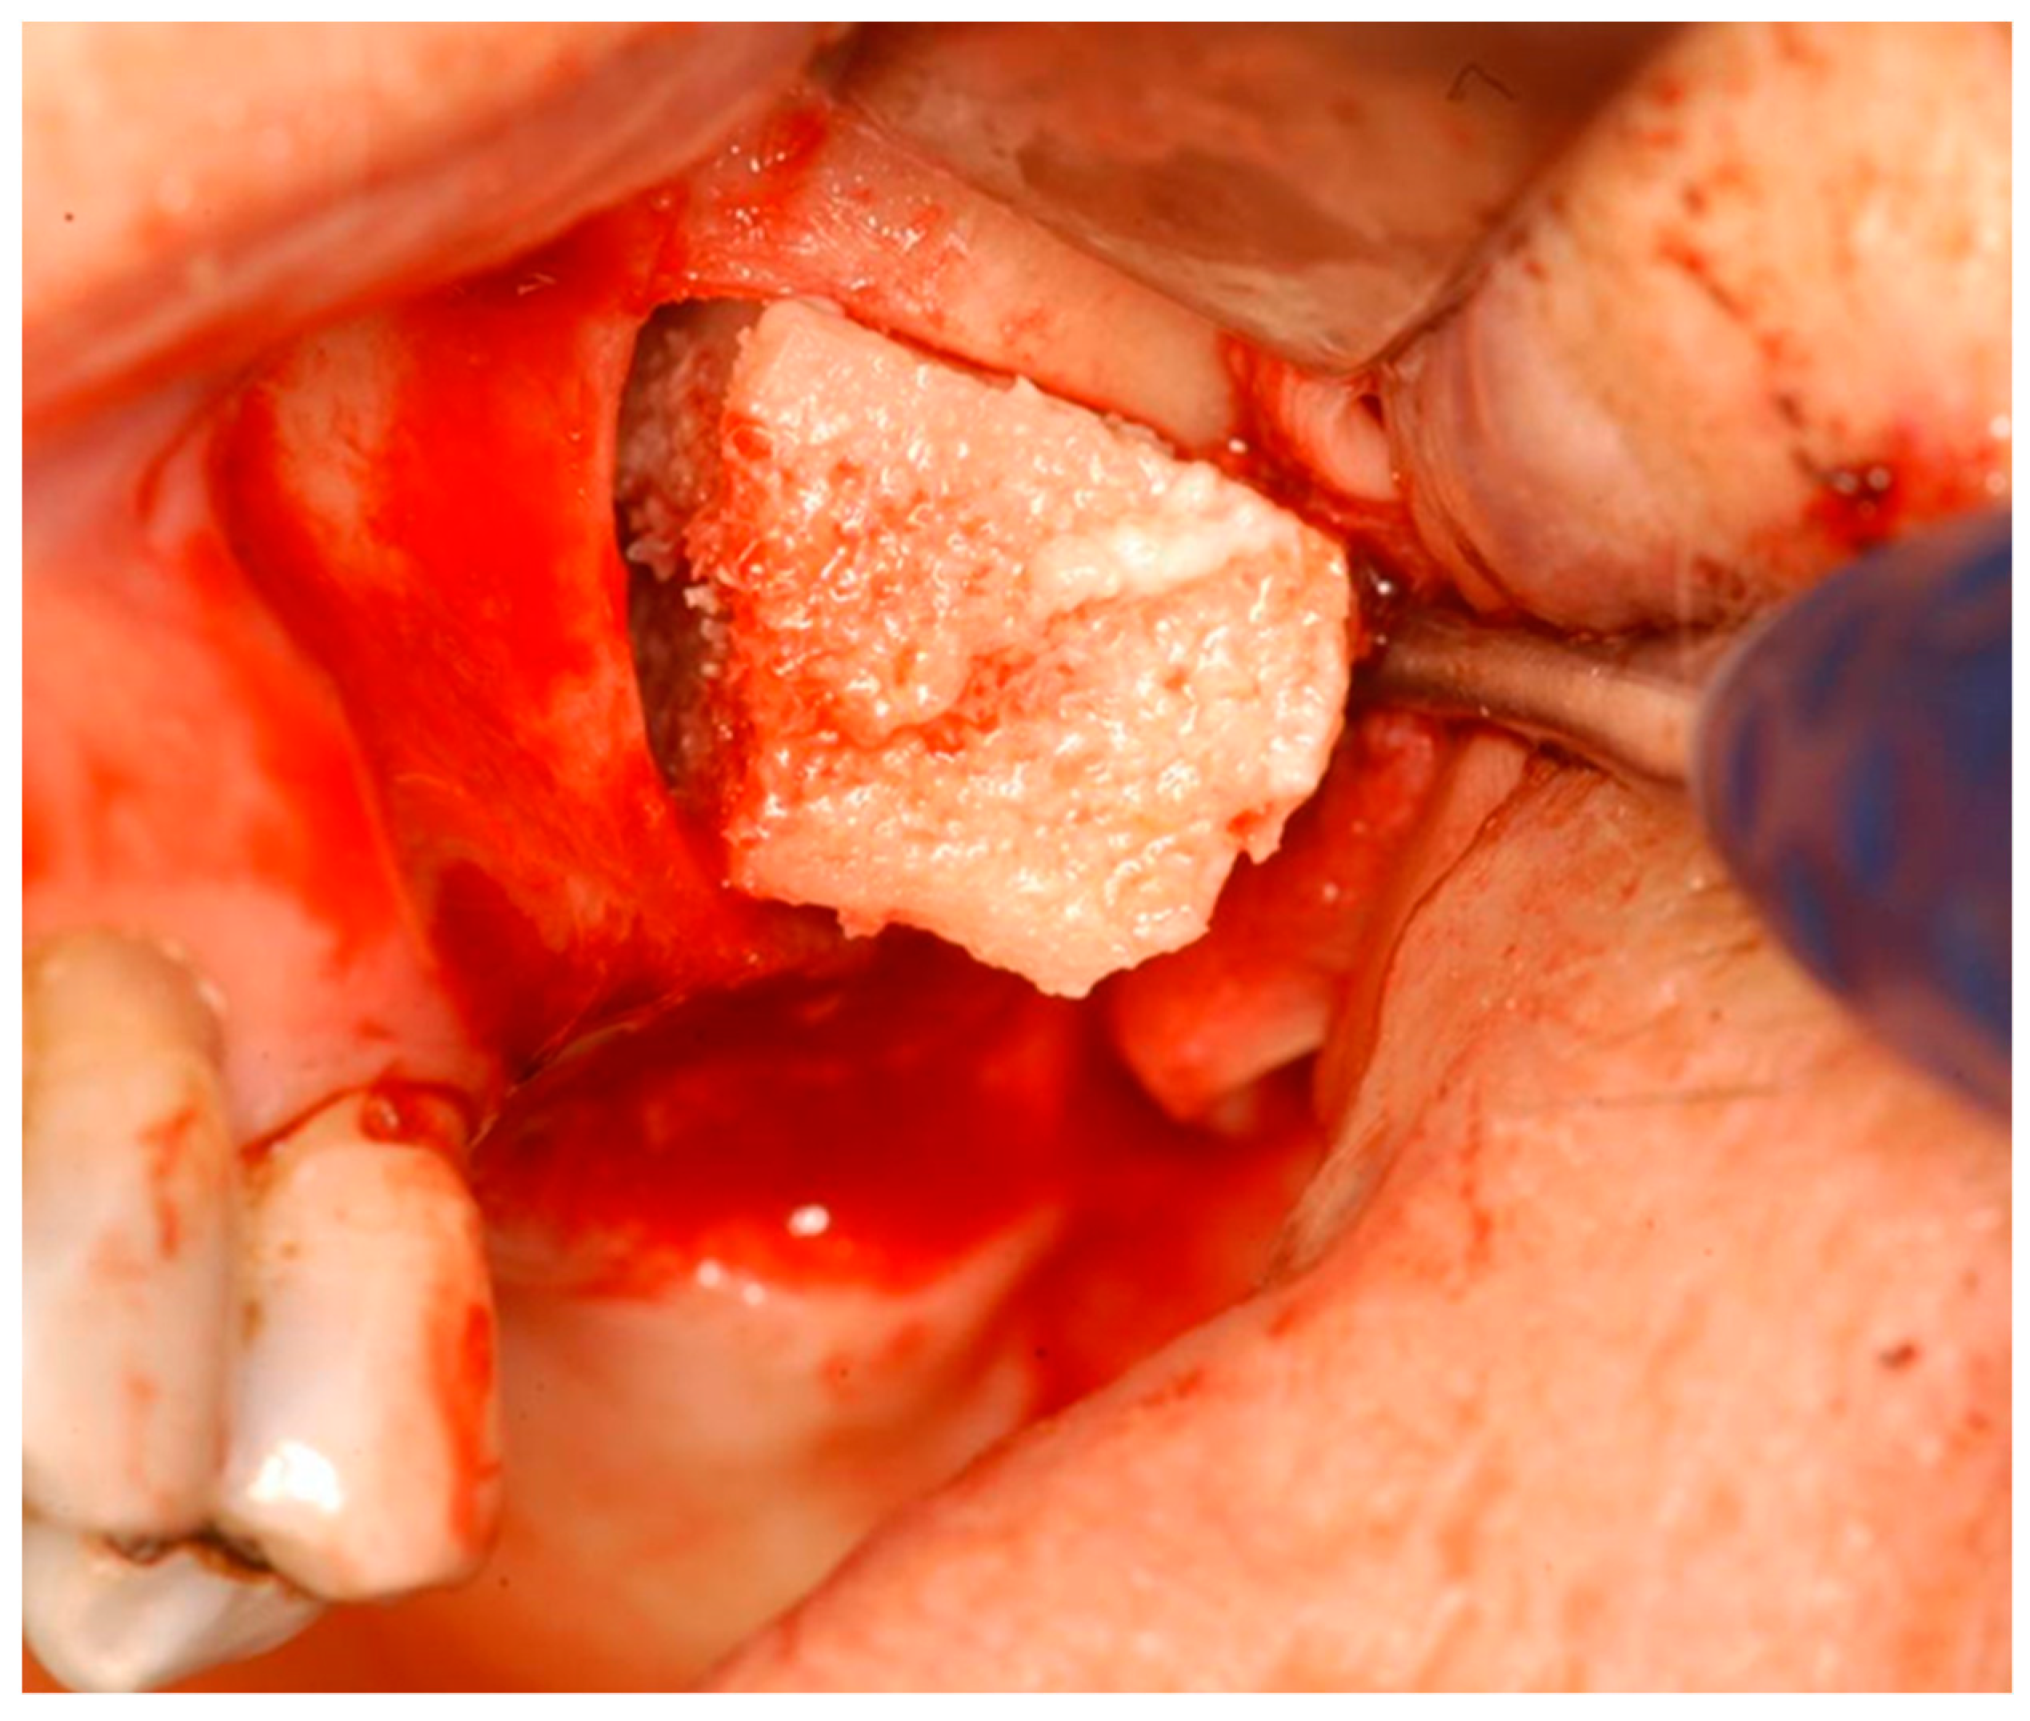

2. Materials and Methods